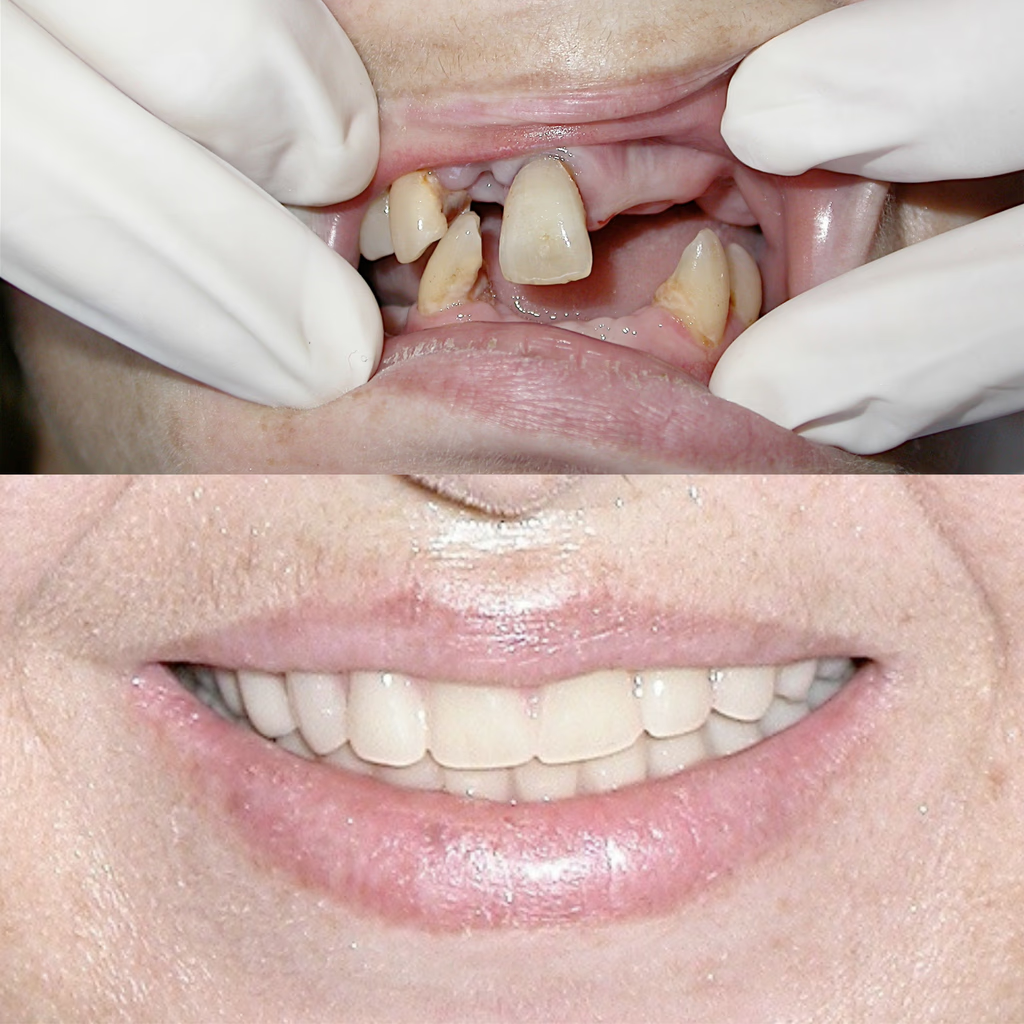

Crown & Bridge Dentistry

When you have a missing tooth or teeth you can have these replaced by a removable denture ,a Bridge which is fixed and not removable or a screw in the tooth called Dental Implant. Bridges have stood the test of time and are a permanent fixed solution to the dilemma of missing teeth.  Dental Implants are probably the best option but can be more expensive  and requires surgery . There are pros and cons to all these modalities. Best to talk to us with your specific issue and we will be happy to advise accordingly.